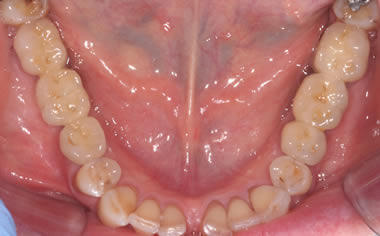

Missing lower teeth replaced by three dental implants and crowns.

Case Two (5 images)

Six missing lower back teeth replaced by dental implants